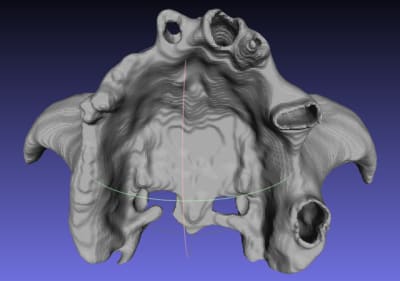

qu'est ce que vous pensez de ce guide, à mon avis il ne nécessite ni irrigation interne ni pins de rétention ( s'il est supra osseux) car rien qu'à l'aide d'un petit coup de marteau il s'enfoncera très bien sur l'Os avec une tres grande précision grace à sa structure trabéculaire.

Je vous invite à voir les autres images sur la Dropbox car elles sont très volumineuses et je n'ai pas pu les importer sur eugenol.

je viens de découvrir que Mialite a l'inconvénient de ne pas garder la meme adresse spatiale des éléments segmentés, c'est a dire que après segmentation des différents éléments: OS,dents, muqueuse, une fois importés à Blender ils ne coincident pas, chaque structure est isolée dans son coin. Je ne trouve pas l'utilité de segmenter avec Mialite.

l'os, les dents et la gencive générés par mialite ne coïncident pas sur blender, Mais

cela a peu d'importance si on veut réaliser un guide a apui osseux, puisque l'on ne va utiliser que le fichier SRL OS pour générer le sinus.

l’état de surface est excellent , de ce fait le guide ne ''s'enfonce'' pas.

si extractions prévues, le guide prend les alvéoles aussi.

bref, je réserves mialite pour les guide osseux